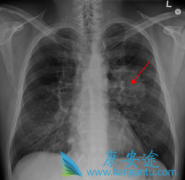

新的免疫药物被批准用于非小细胞肺癌治疗

春节期间,美国食品药品监督管理局(FDA)批准PD-L1免疫药物 Imfinzi (durvalumab)上市,用于治疗无法进行手术切除的局部晚期 非小细胞肺癌 患者。代号为PACIFIC(太平洋)的Imfinzi三期临床研究结果结果表明:对于无法进行手术切除的局部晚期肺癌患者, ...